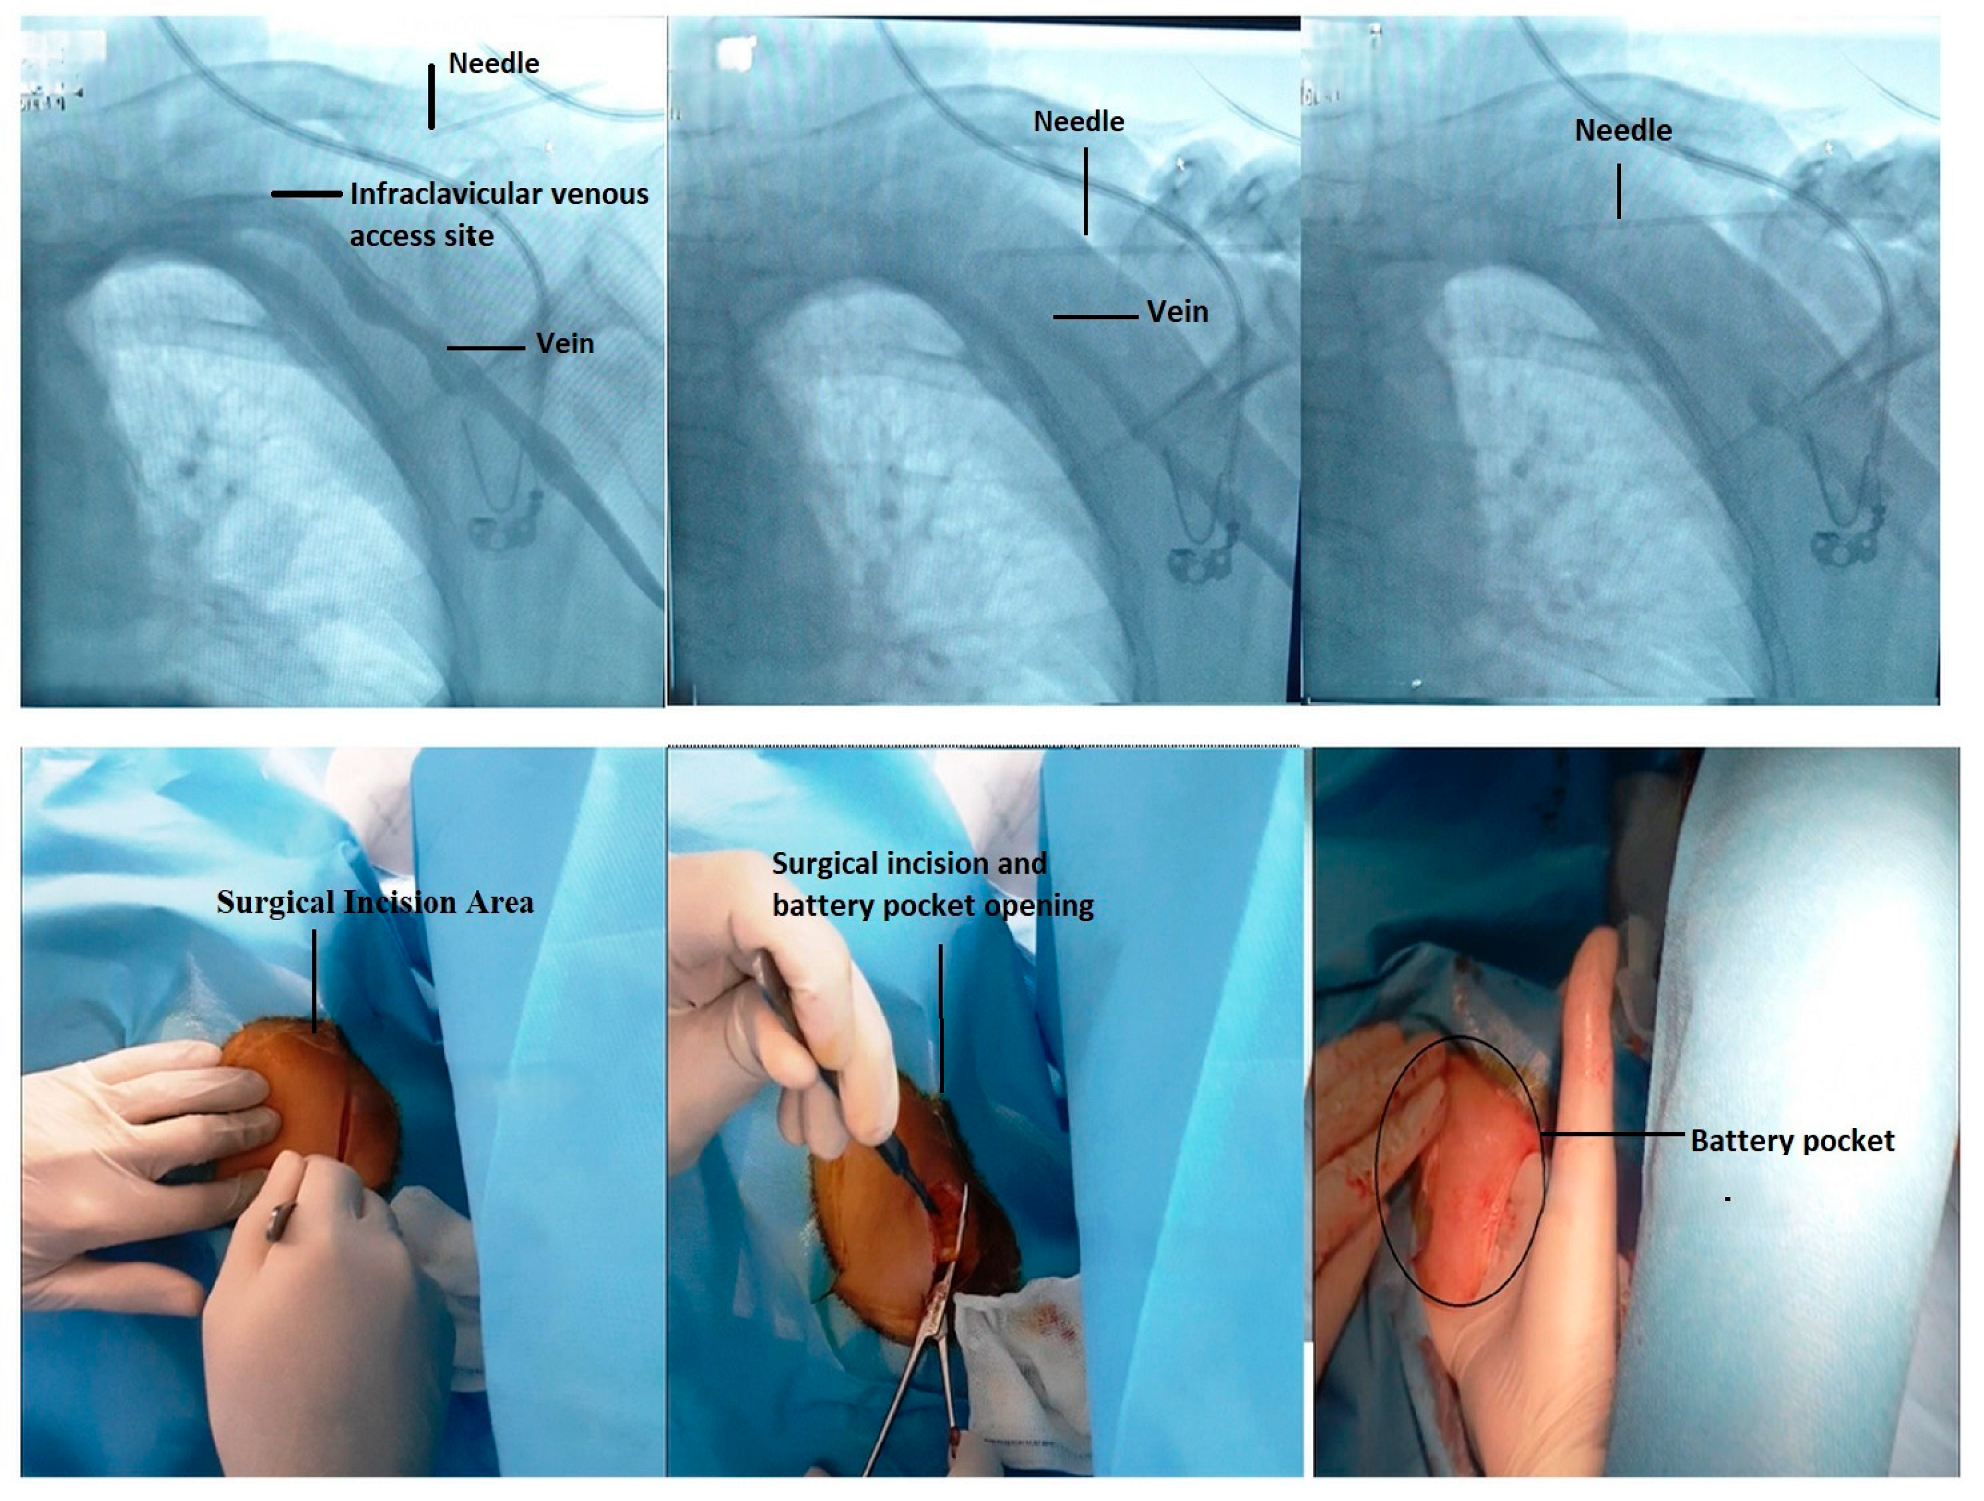

4.1. Fluoroscopic-Guided Vascular Puncture in Posterior–Anterior (PA) Projection